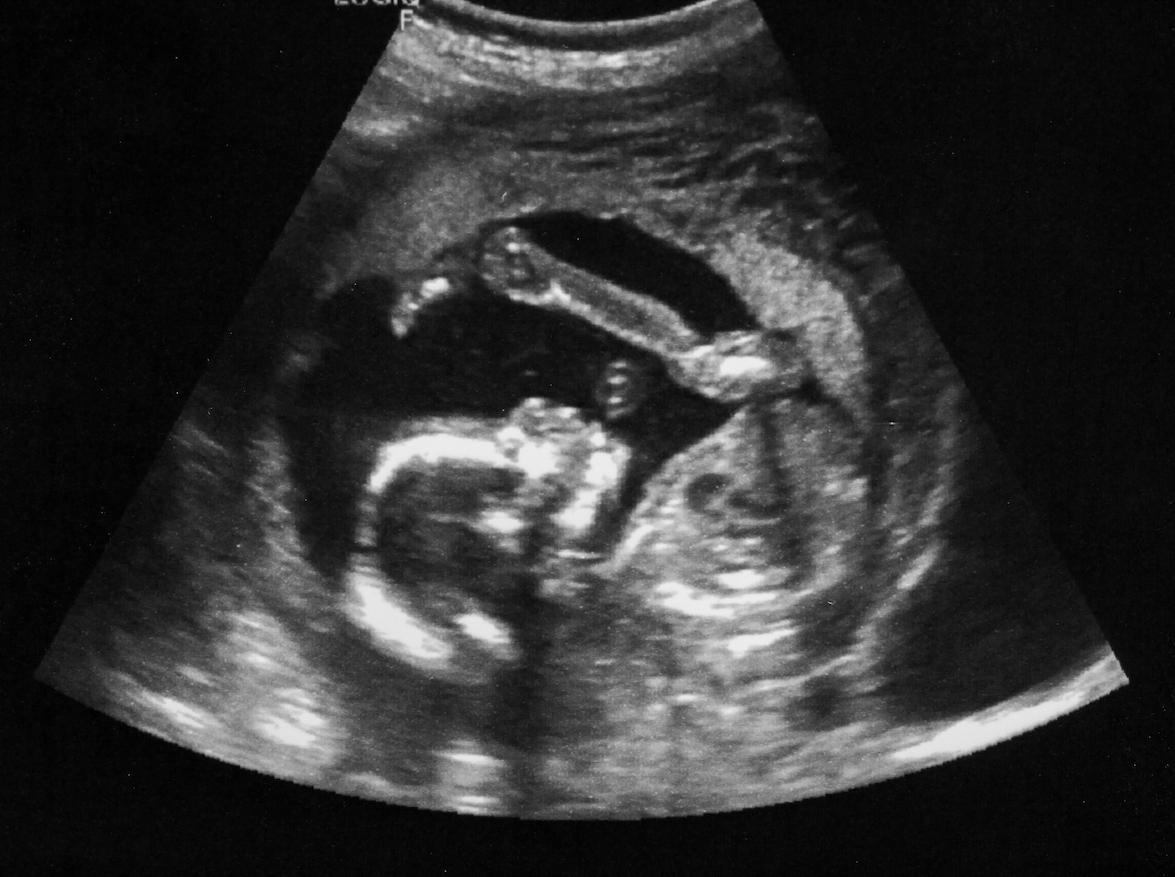

Pour cette étude, les chercheurs se sont spécifiquement concentrés sur les troubles du spectre autistique liés aux auto-anticorps maternels, qui représentent environ 20% des tous les cas d’autisme. En effet, les auto-anticorps sont des protéines immunitaires qui attaquent nos propres tissus. Dans une précédente étude, les chercheurs s’étaient déjà aperçu que les auto-anticorps des mères enceintes pouvaient interagir avec le cerveau de leur fœtus en pleine croissance et en modifier son développement.